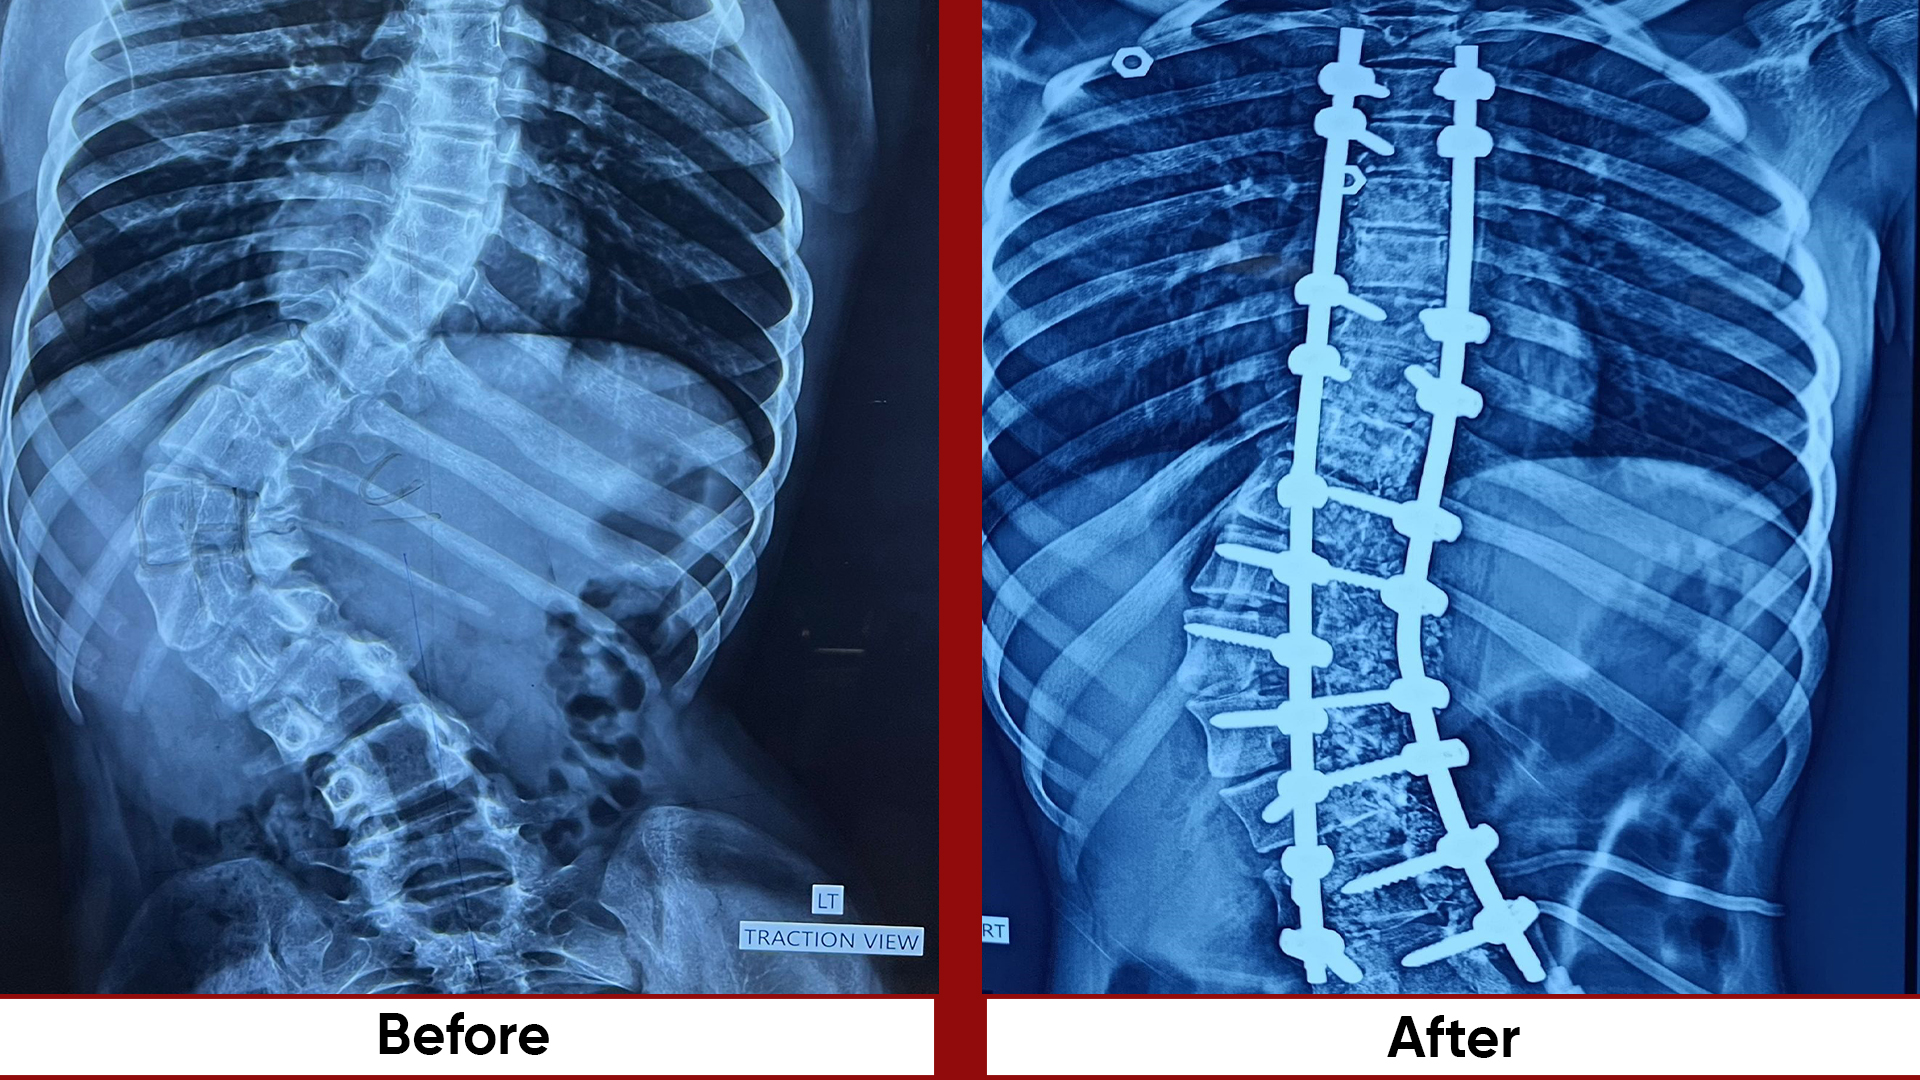

• Spine: Trauma Deformity –EOS AIS-Adult deformity, all fractures operated within 24/7.